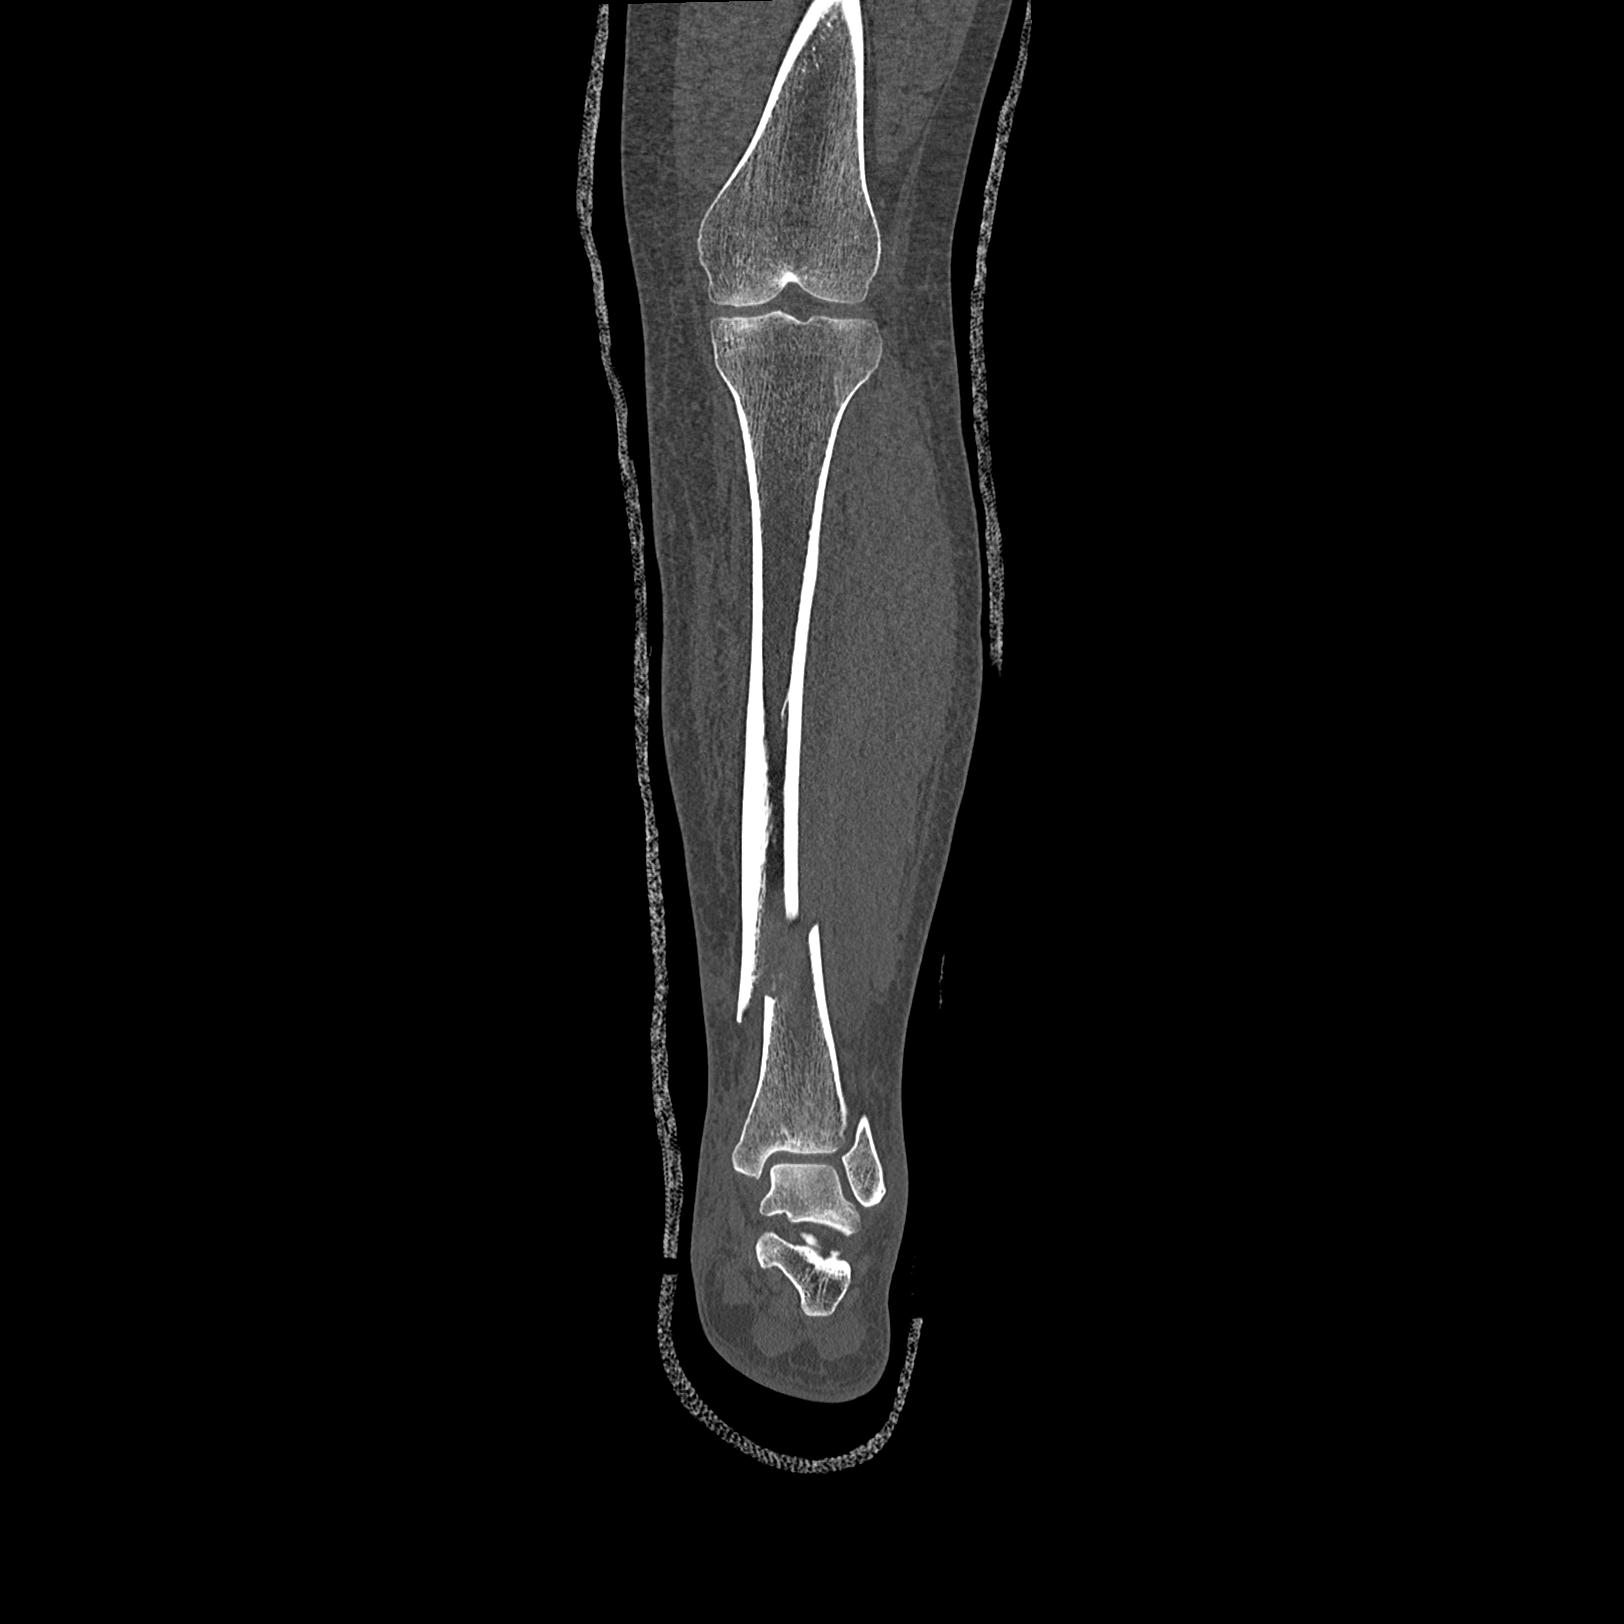

102803 1/12(キウスなし) 1/27 左下腿 4R 30歳女性 左脛骨軸内釘